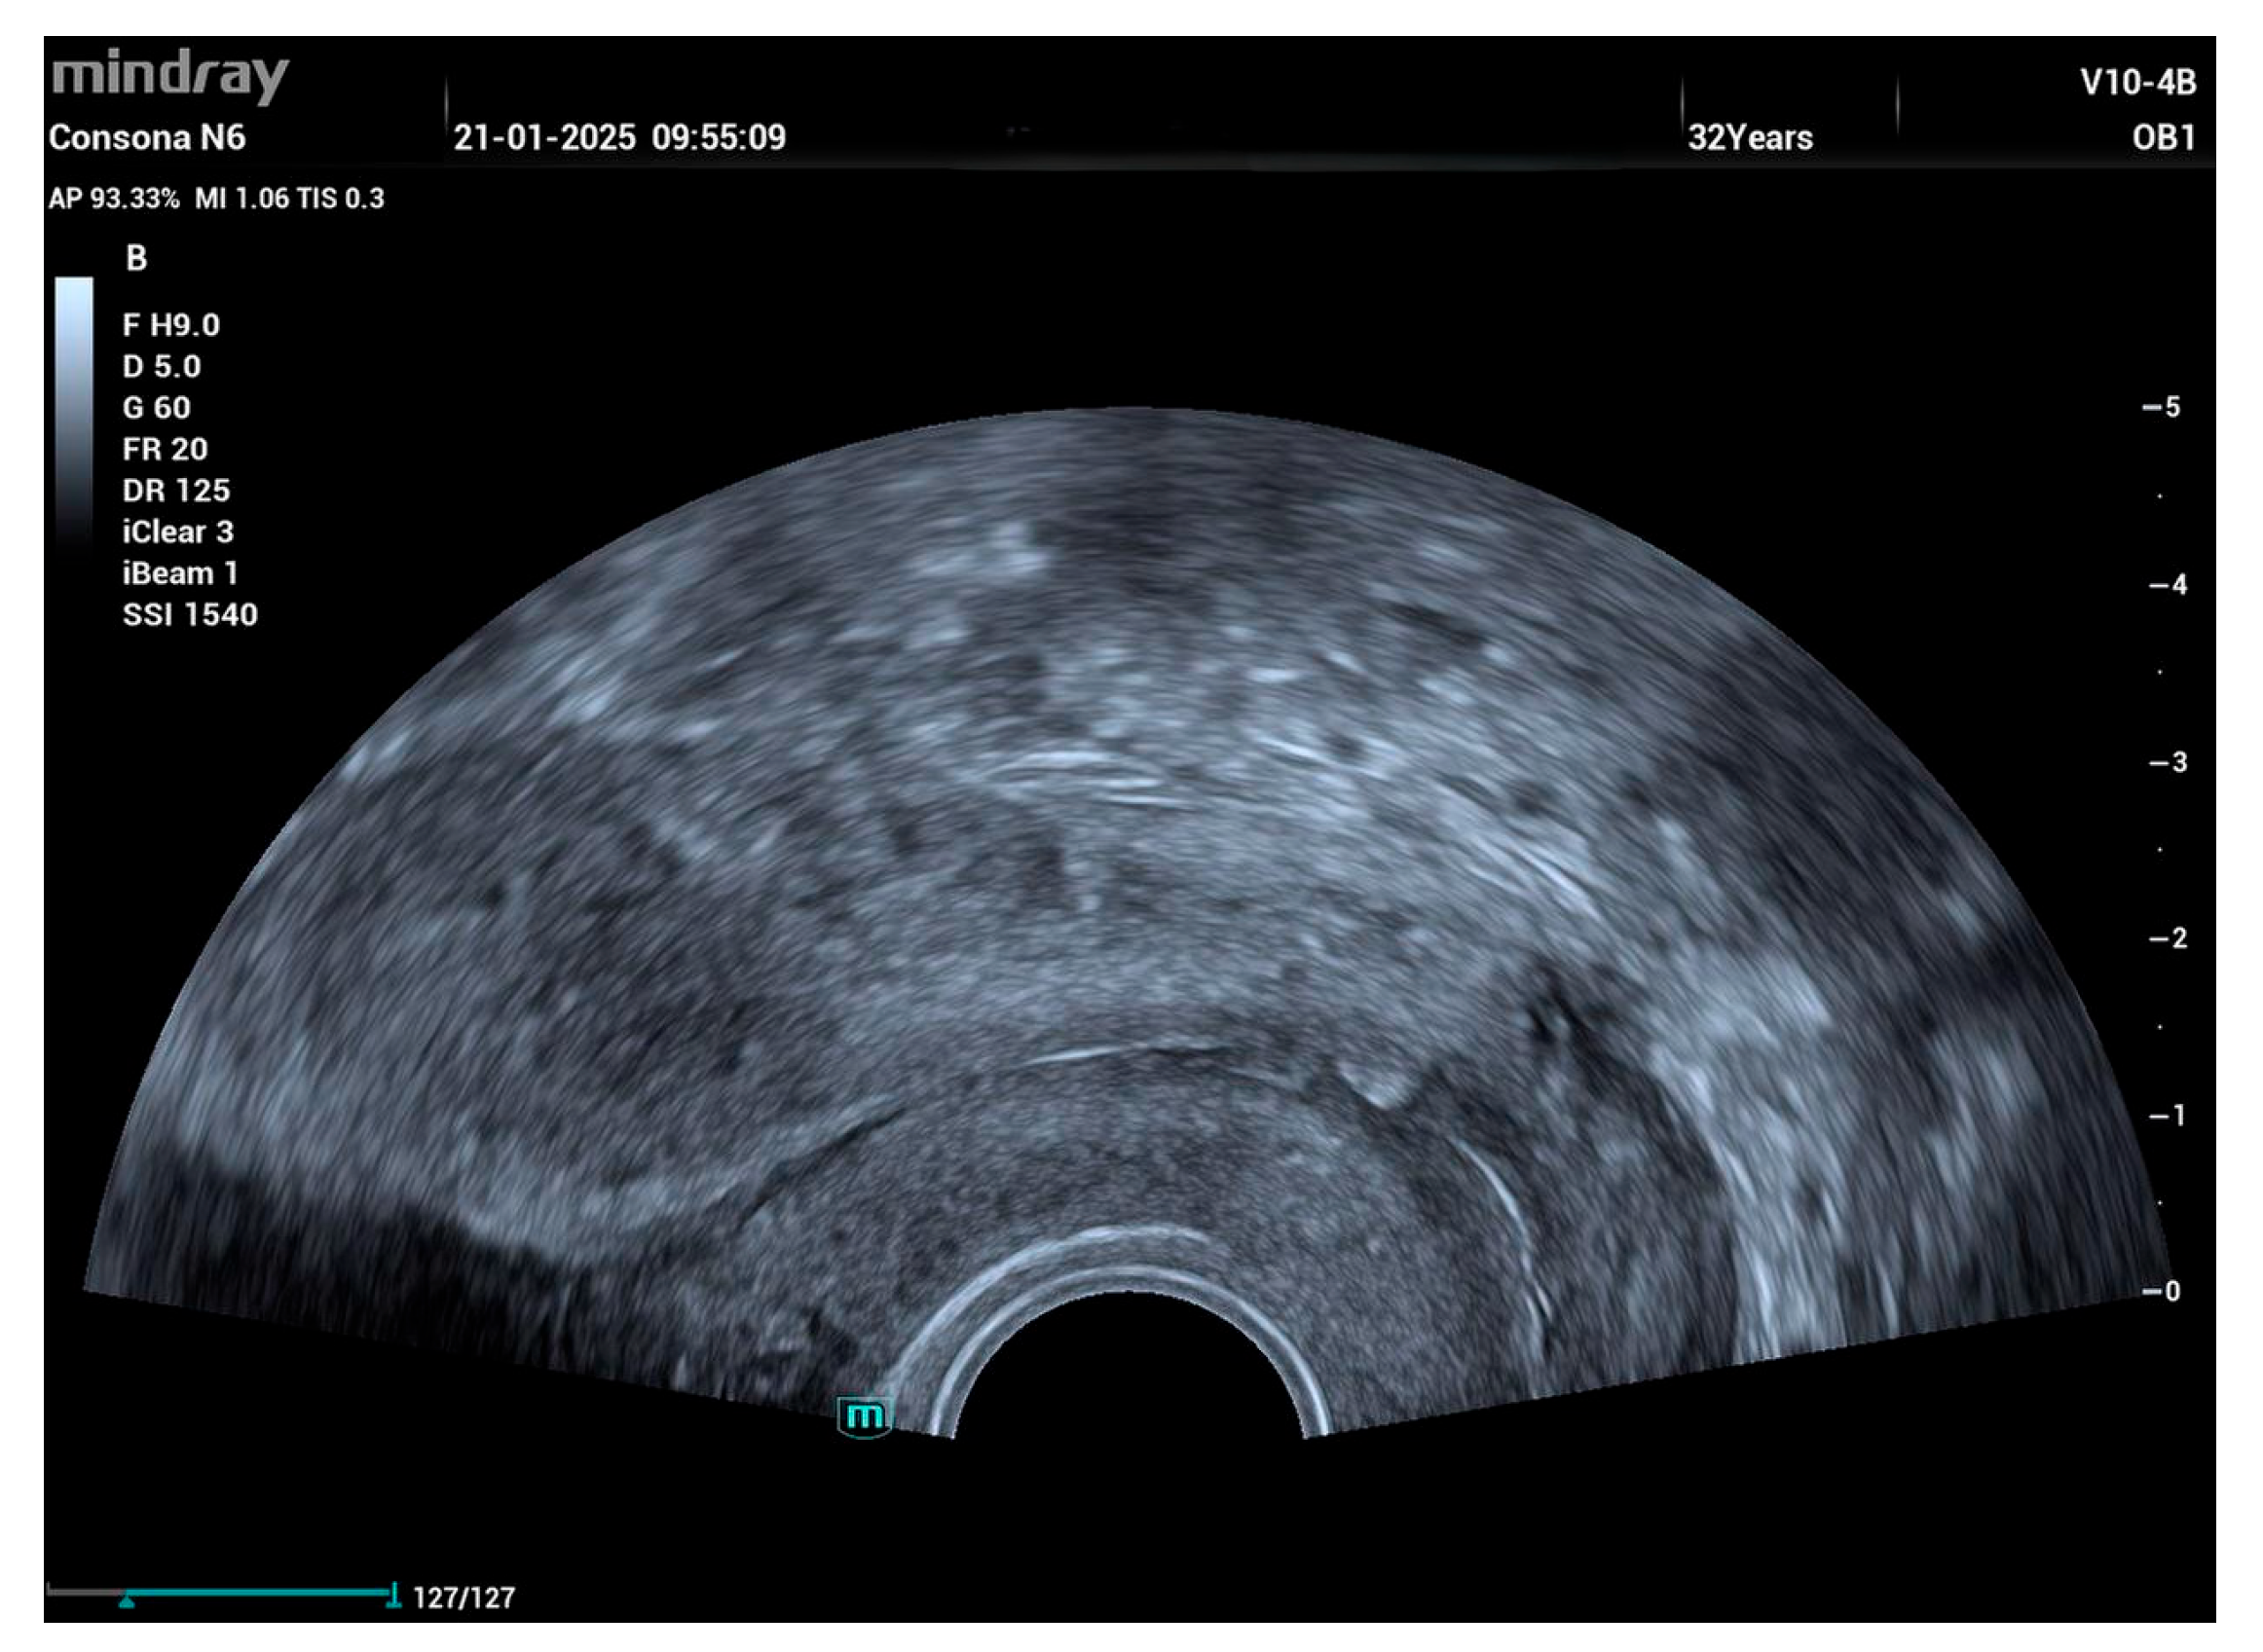

An ultrasound on day 11 post-op showed normal healing with no abnormalities (Figure 4).

Figure 4. Normal ultrasound view of endometrial cavity and cervical canal.